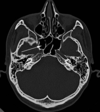

Head And Neck Flashcards

(292 cards)